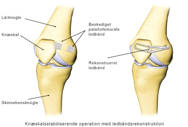

Hvis knæskallen har været gået af led, er ledbåndet fra knæskallen til lårbenets inderside også beskadiget. Selv om ledbåndet heler sammen igen, vil det for hver gang knæskallen går af led, blive slappere og miste evnen til at holde igen på knæskallen. Derfor må man lave en rekonstruktion af ledbåndet.